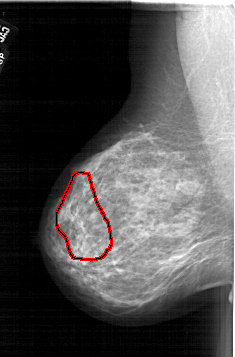

A_1668_1.RIGHT_CC

RIGHT_CC LINES 6151 PIXELS_PER_LINE 3916 BITS_PER_PIXEL 12 RESOLUTION 43.5 NON_OVERLAY

FILE: A_1668_1.LEFT_MLO.OVERLAY

TOTAL_ABNORMALITIES 1

ABNORMALITY 1

LESION_TYPE CALCIFICATION TYPE PLEOMORPHIC DISTRIBUTION SEGMENTAL

ASSESSMENT 4

SUBTLETY 3

PATHOLOGY MALIGNANT

TOTAL_OUTLINES 1

BOUNDARY